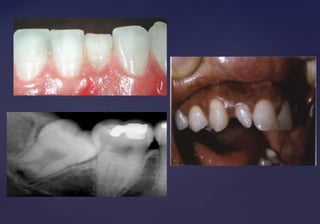

TAURODONCIATAURODONCIA

 Molar con una corona alargada y situada enMolar con una corona alargada y situada en

posición apical respecto a la bifurcación de lasposición apical respecto a la bifurcación de las

raíces que da por resultado una cámara pulparraíces que da por resultado una cámara pulpar

coronal rectangular de tamaño mayor que elcoronal rectangular de tamaño mayor que el

normal.normal.

 Causada por la desorganización de los tejidosCausada por la desorganización de los tejidos

descalcificados.descalcificados.

 Fuerzas excesivas durante la masticación.Fuerzas excesivas durante la masticación.

 Afecta los molares, ocasionalmente losAfecta los molares, ocasionalmente los

premolares.premolares.

 Afecta dientes permanentes y deciduos.Afecta dientes permanentes y deciduos.